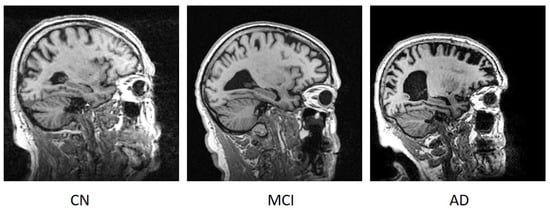

3.1. Data and Tools

| Classes | Subjects | Age (Years) | Training Images | Testing Images | Total No. Images |

|---|---|---|---|---|---|

| CN | 50 | 60–69 | 900 | 350 | 3750 |

| 70–79 | 900 | 350 | |||

| 80+ | 900 | 350 | |||

| MCI | 50 | 60–69 | 900 | 350 | 3750 |

| AD | 50 | 60–69 | 900 | 350 | 3750 |

| Total | 150 | 8100 | 3150 | 11,250 | |